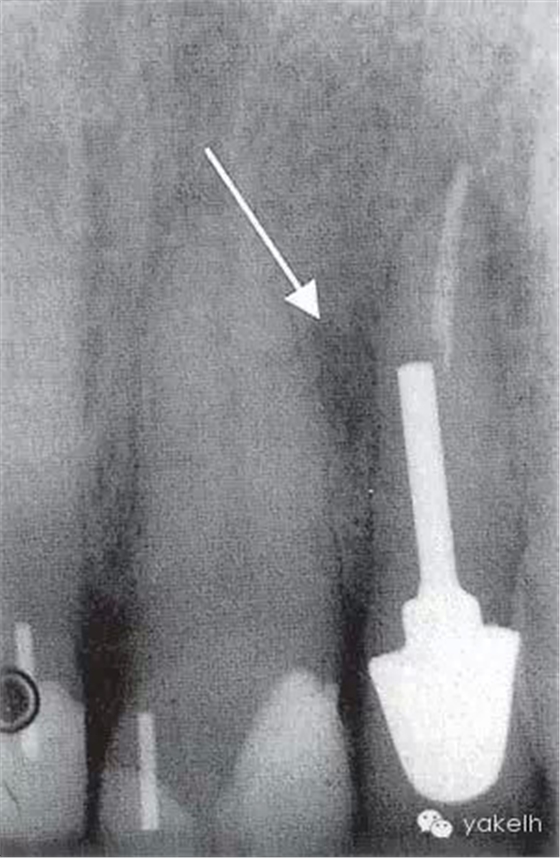

¤¤口外檢查可見顳下頜關(guān)節(jié)處輕微捻發(fā)音,開口度、開口型正常,無疼痛,未見其他異常。口內(nèi)檢查可見牙列中有部分良好的修復(fù)體,無齲壞;局部牙齦炎,探診出血,牙周探診深度不超過2mm。22唇側(cè)牙槽黏膜可見竇道(圖5.4.1a),輕微叩痛,竇道區(qū)捫痛,根尖X線片顯示牙根中部透射影,疑為樁穿孔(圖5.4.1b)。左上頜中切牙(21)和左上頜尖牙(23)對EPT和冷測試反應(yīng)正常。

圖 5.4.1(b)22根尖X線片,顯示樁穿孔側(cè)方的根周透射影。